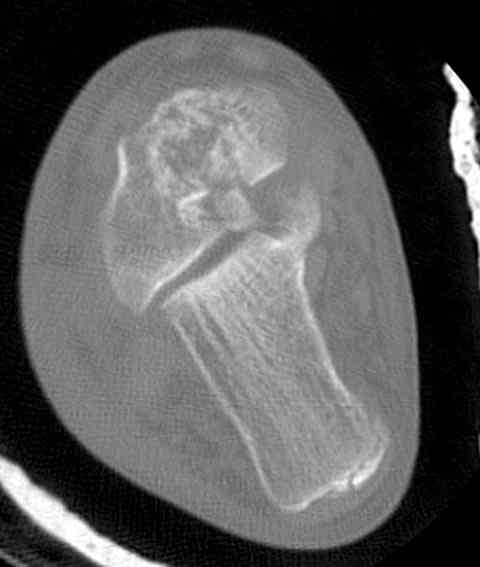

Случай с множественным оскольчатым переломом тарана оперированный из двойного доступа.

Через 14 мес.: